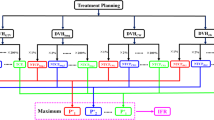

Given the strong and significant correlations observed among all dosimetric variables in the preceding section and the literature, it is more appropriate to condense the various dosimetric variables into a single representative dose parameter for the analysis of NTCP of RP. As previously mentioned, MI, which exhibited "strong" or "very strong" correlations with other dosimetric variables, can be considered the most suitable choice for the representative dose parameter.

This section employed a machine learning method, linear regression, to clarify the relationships among different dose distribution variables. All dose distribution data in this cohort were divided into a training set and a test set, with the test set accounting for 12% of each dataset. A "random_state" parameter was utilized to ensure result consistency for every linear regression model. The fitting results are depicted in Fig. 3 and Table 3. The parameters w and b represent the slope and intercept of the linear regression model, respectively.

For IL and TL, V5, V10, V20, V25 and V30 could be linearly represented by their corresponding MD. Apart from the MSE for V5 of IL versus MI, which exceeded 9, other regression results were quite satisfactory, with MSE less than 3 and R2 greater than 0.80. Due to smaller tumor sizes and stricter dose limitations in SBRT compared to CFRT for lung cancers, the delivered dose to the CL was relatively low. This was directly reflected in the percentage of volume receiving a dose greater than 10 Gy of CL, which was approximately zero. Thus, only regression algorithms for V5 and V10 versus MC were performed, with MSE and R2 values of 2.89, 0.94 and 0.59, 0.80 for V5 and V10, respectively.

Another exciting discovery was that both MT and MC could be linearly expressed by MI, with MSE and R2 values of 0.04 and 0.97 for MT, and 0.02 and 0.88 for MC, respectively. In summary, in SBRT of lung cancers, the Vd for IL, MT, and MC could be linearly represented by MI with a good fit. Furthermore, MT and MC could linearly express the Vd of TL and CL. Thus, according to MI, all dose distributions of IL, CL and TL in SBRT for lung cancers can be linearly predicted.

Baker et al.18 previously proposed that the ratio of PTV to normal lung volume was highly significant for developing RP2 in SBRT for lung cancers. However, their study did not describe the relationship between the ratio and RP2 or dosimetric data. Based on this, the lung tumor ratio (LTR), defined as the volume of IL divided by PTV, was introduced in this section to combine the information of PTV and the volume of IL. Its value ranged from 9.18 to 151.97, with a median of 36.26 and a mean of 44.88 in the cohort. Figures 6 illustrate that compared to the PTV or the volume of IL, the LTR was a more reliable predictive factor for MI. The fitting curve could be expressed as a power function, with MSE and R2 being 13.51 and 0.62, respectively. Namely, MI decreased as a power exponential of the LTR. Thus, in this study, the LTR can be used to predict MI, and then MI can be used to calculate the Vd of IL, MC, and MT. Furthermore, the Vd of CL and TL can be obtained by MC and MT, respectively. Overall, the LTR was a suitable predictor for MI and could be used to predict all dose distributions in SBRT for lung cancers.

It is important to note that although all dosimetric parameters have demonstrated a good correlation with the incidence of RP in references10,29,33, it has become a consensus that MT (i.e., MLD in references) is the best predictor of RP. In this cohort, for each patient, the DVH of their lungs (including MT) can be simplified to a single parameter (MI), which is a dependent variable of LTR as described in the preceding section. Therefore, utilizing the LTR to predict the probability of RP will significantly streamline the construction process of its NTCP model. Referring to Table 3, MT can be expressed as a function of MI:

Furthermore, as depicted in Fig. 5, MI can be predicted by the LTR:

Hence, based on the MT model and the combined formulas (4), (5) and (6), the integration variable of NTCP for RP can be expressed as a function of the LTR: